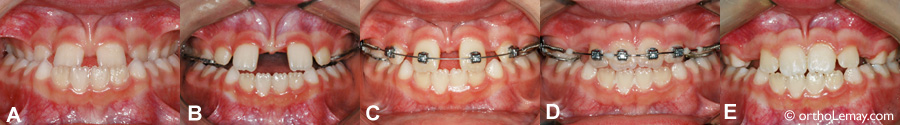

Fermeture d’espaces et de diastèmes

Lorsqu’un diastème important est présent avant un traitement d’expansion maxillaire, ce diastème augmentera significativement. Après l’expansion, il pourra être refermé à l’aide de à l’aide de quelques boîtiers et un élastique.   ➡ Pour voir d’autres exemples de fermeture de diastèmes et des cas particuliers.